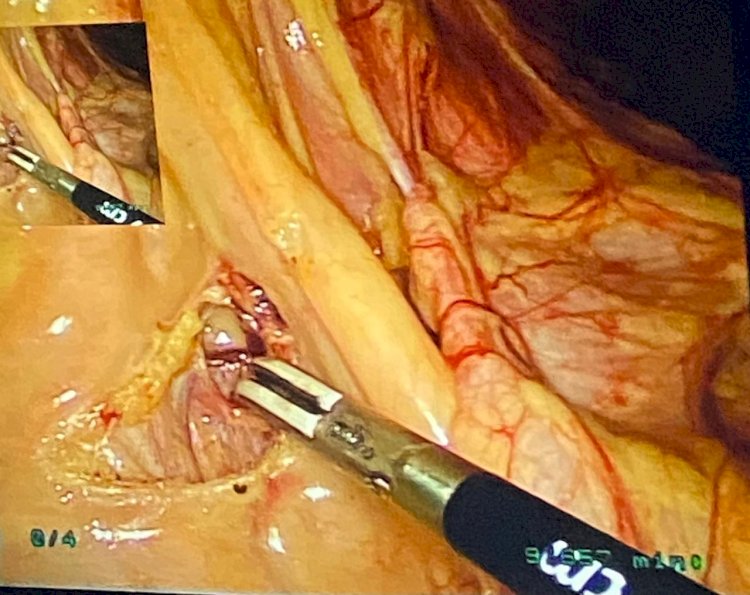

صرح الدكتور حسان النعماني رئيس جامعة سوهاج ان فريق طبي بقسم الجراحة العامة بالمستشفى الجامعي نجح في استئصال ورم بالقولون طوله ١٠ سم لمريض يبلغ من العمر ٦٥ عام بواسطة المنظار الجراحي، وذلك دون اللجوء الي الجراحه المعتادة و التي تتم عادة بواسطة جرح استكشافي بالبطن و التي قد تؤدي بقاء المريض فترة أطول بالمستشفي.

وأوضح الدكتور مجدي القاضي عميد كلية الطب البشري ورئيس مجلس ادارة المستشفيات الجامعية ان المريض يعاني من ورم سرطاني بالقولون الصاعد حيث تم إجراء الأشعات والتحاليل اللازمة و اجراء التدخل الجراحي بواسطة المنظار، ثم استئصال الجزء الأيمن للقولون مع الغدد الليمفاوية كاملة واعادة توصيل الأمعاء والدباسات الجراحية.

وأضاف الدكتور علاء السيوطي رئيس قسم الجراحه العامة ان تلك الجراحة تعد تطور جديد في جراحات الأورام، حيث خرج المريض من المستشفى بعد تمام الشفاء، مشيراً الي انه أجري الجراحة الدكتور مينا ظريف استاذ مساعد الجراحة وجراحة الاورام والمناظير مع الفريق الطبي الذي ضم الدكتور اسامة صالح مدرس مساعد، الدكتور احمد محروس مدرس مساعد والدكتور اسلام ابو الدهب طبيب مقيم واطباء التخدير وهيئة التمريض.